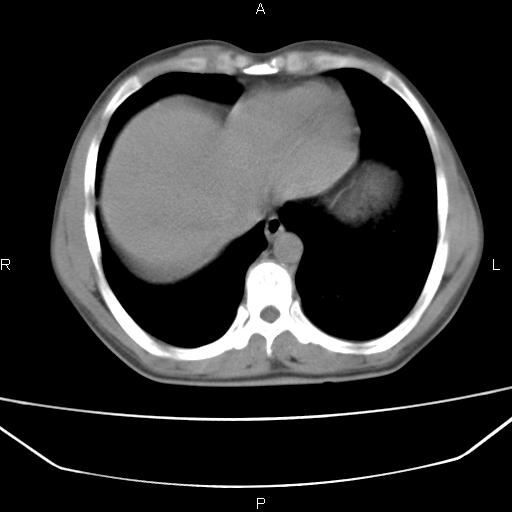

患者,男,40岁。间断发热,咳嗽二十余日。体温最高达38.9° 在当地诊所抗炎治疗三天后体温降至正常,患者自行停药。今又发热。胸片示,左下肺阴影。

左下肺片状高密度影,境界模糊,密度不均,考虑感染性病变可能性大,建议抗炎治疗后复查。左肺门增大,不除外占位性病变,必要时支气管镜检。